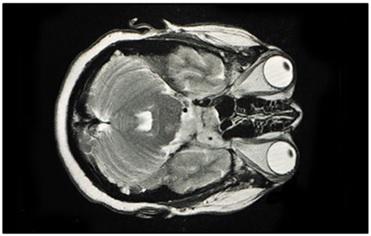

MRI stands for Magnetic Resonance Imaging. This technology relies on magnetism. It’s a more recent advancement compared to CT scans. MRI uses magnetism to create a 3D image of the body’s interior.

Similar to CT scanners, MRI machines have a moving platform. Patients lie down on this platform and are moved into a narrow cylinder. Magnets within the cylinder generate a strong magnetic field around the patient’s body. The cylinder is somewhat narrower compared to CT scanners. It’s crucial to remove all metallic objects from the body before an MRI scan. MRI scans can take around 30 minutes to complete.